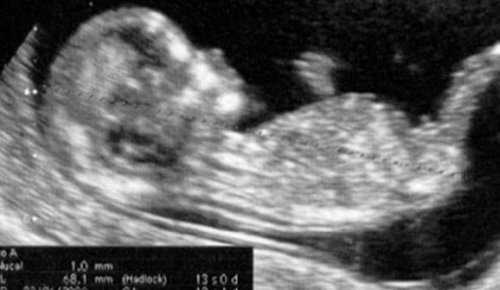

Alla tredicesima settimana di gravidanza è ancora possibile realizzare, se non è stata ancora fatta, l’ecografia della fine del primo trimestre. È il passo finale dei controlli a cui bisogna sottoporsi appena si scopre di essere in attesa. È il momento nel quale si conclude la valutazione del primo trimestre e si potrebbe dire che la parte più difficile e angosciante (soprattutto per le primipare) è ormai passato.